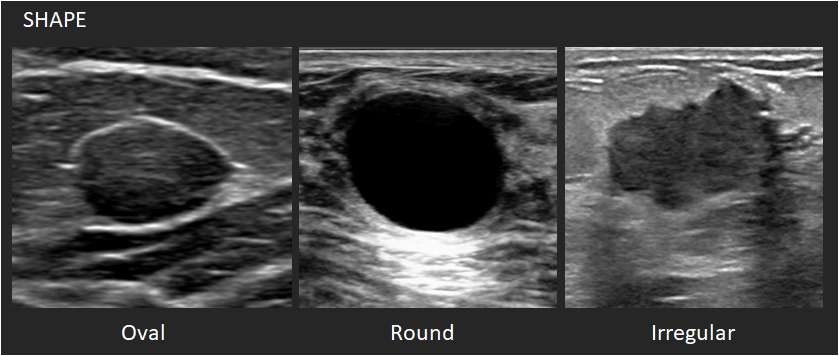

유방암 수술 시에는 수술 전 MRI나 초음파 검사를 통해 종양의 위치와 범위를 정확히 파악하며, 필요할 경우 조직검사를 통해 세포의 악성도나 호르몬 수용체 여부를 분석합니다. 이러한 사전 검사는 치료 방향을 결정하는 데 핵심적인 역할을 합니다. 의료진은 환자 개개인의 상황에 맞춰 절제 범위와 수술 방법을 결정하고, 재건 여부를 함께 계획합니다.